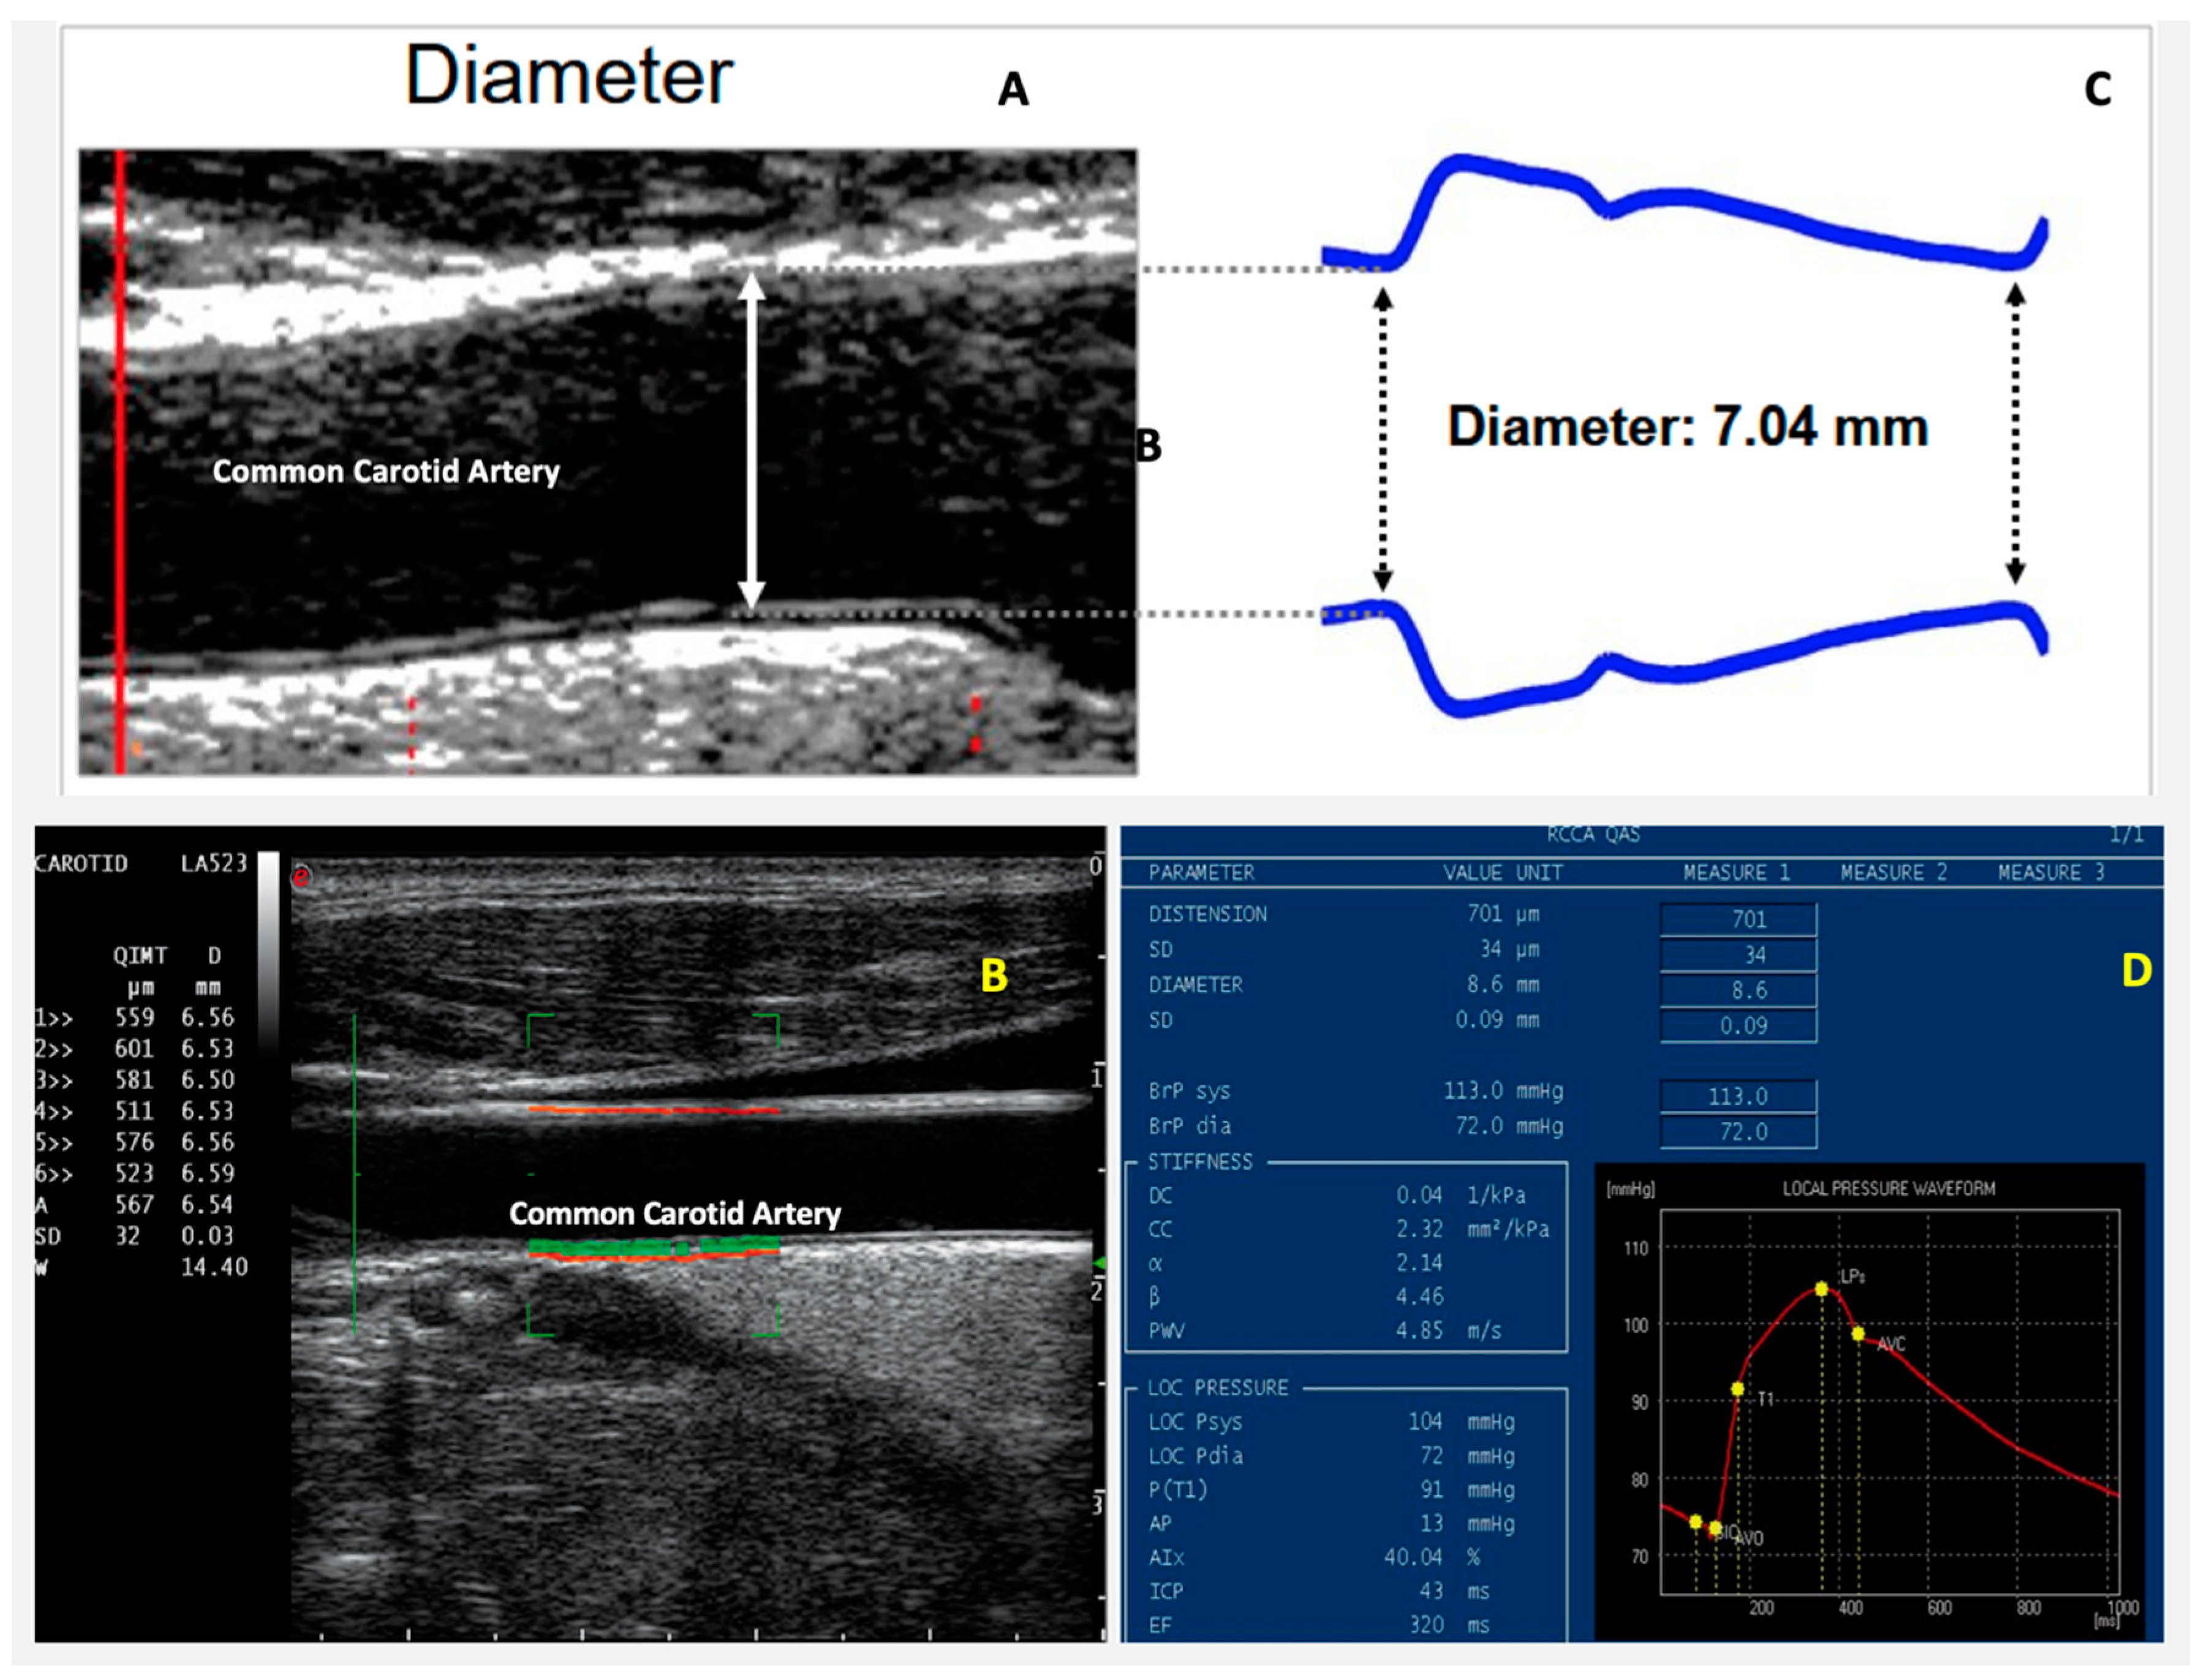

7. Arterial Stiffness

Role of Arterial Stiffness in IHD

- Feola, M.; Testa, M.; Ferreri, C.; Rosso, G.; Rossi, A.; Ruocco, G. The analysis of arterial stiffness in heart failure patients in comparison with healthy subjects and patients with cardiovascular risk factors. J. Clin. Med. 2019, 8, 1721. [Google Scholar] [CrossRef] [PubMed]

- Ikonomidis, I.; Makavos, G.; Lekakis, J.P. Arterial stiffness and coronary artery disease. Curr. Opin. Cardiol. 2015, 30. [Google Scholar] [CrossRef] [PubMed]

- Mitchell, G.F.; Hwang, S.-J.; Vasan, R.S.; Larson, M.G.; Pencina, M.J.; Hamburg, N.M.; Vita, J.A.; Levy, D.; Benjamin, E.J. Arterial stiffness and cardiovascular events: The Framingham heart study. Circulation 2010, 121, 505–511. [Google Scholar] [CrossRef] [PubMed]

- Vlachopoulos, C.; Aznaouridis, K.; Stefanadis, C. Prediction of cardiovascular events and all-cause mortality with arterial stiffness: A systematic review and meta-analysis. J. Am. Coll. Cardiol. 2010, 55, 1318–1327. [Google Scholar] [CrossRef]

- Kaneko, H.; Yajima, J.; Oikawa, Y.; Matsuno, S.; Funada, R.; Tanaka, S.; Fukamachi, D.; Suzuki, S.; Aizawa, T.; Yamashita, T. Role of arterial stiffness and impaired renal function in the progression of new coronary lesions after percutaneous coronary intervention. Cardiovasc. Interv. Ther. 2012, 28, 56–62. [Google Scholar] [CrossRef]

- Nakamura, M.; Yamashita, T.; Yajima, J.; Oikawa, Y.; Sagara, K.; Koike, A.; Kirigaya, H.; Nagashima, K.; Sawada, H.; Aizawa, T.; et al. Brachial-ankle pulse wave velocity as a risk stratification index for the short-term prognosis of type 2 diabetic patients with coronary artery disease. Hypertens. Res. 2010, 33, 1018–1024. [Google Scholar] [CrossRef]

- Regnault, V.; Lagrange, J.; Pizard, A.; Safar, M.E.; Fay, R.; Pitt, B.; Challande, P.; Rossignol, P.; Zannad, F.; Lacolley, P. Opposite predictive value of pulse pressure and aortic pulse wave velocity on heart failure with reduced left ventricular ejection fraction: Insights from an Eplerenone Post-Acute Myocardial Infarction Heart Failure Efficacy and Survival Study (EPHESUS) substudy. Hypertension 2014, 63, 105–111. [Google Scholar] [CrossRef]